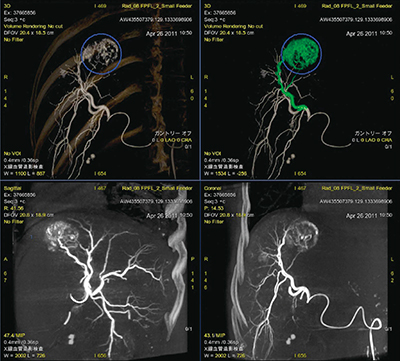

3.腫瘍濃染の選択

各種3D画像や各断面画像を適宜比較しながら,腫瘍濃染の大きさに応じて円形カーソルのサイズを調整しつつ,濃染位置を決定する。その後,濃染位置と肝動脈近位部との連続性の高い信号,すなわち,栄養血管と思われる信号を自動検出し,VR画像上で緑色に表示する(図4)。血管自体の描出能を妨げることを危惧し,あくまでも色のみを変化させ補助ラインなどは表示しない。かつ,FPFLによる探索結果とともに,MIP画像やVR画像,ならびに各断面画像を同時表示することにより,術者自身が栄養血管に関して総合的な判断が行えるように画像がレイアウトされている。

図4 FlightPlan for Liver